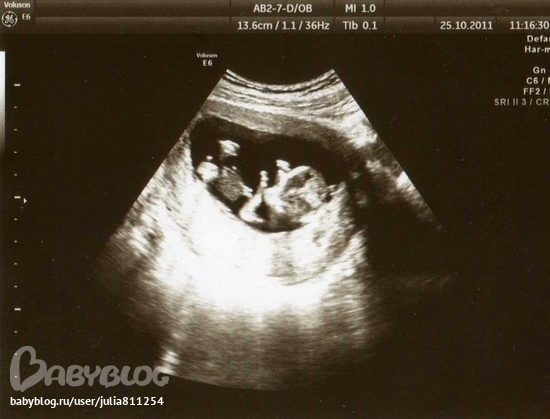

Третье узи в 12-13 недель делала платно, результат: КТР 58мм, ТВП 1,3,плацента по задней стенке, толшиной 13, а самое главное - МАЛЬЧИК.